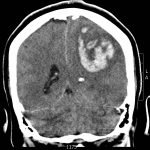

The patient’s head CT showed a significant area of hyperdensity consistent with an intracranial hemorrhage located within the left frontal parietal lobe (red arrow). Additionally, there is rightward midline shift up to 1.1cm (green arrow) and entrapment of the right lateral ventricle (blue arrow).